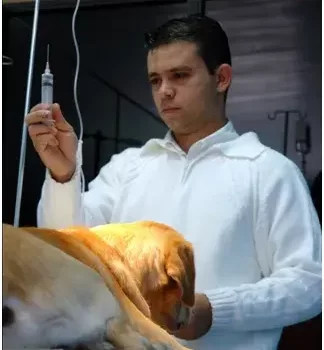

Antes de mais nada, o Veterinário é o profissional responsável por garantir a saúde e o bem-estar dos animais, atuando desde a prevenção até o tratamento de doenças. Importância do Veterinário para a saúde animal Em primeiro lugar, o Veterinário desempenha papel essencial na detecção precoce de doenças, o que […]

Antes de mais nada, a Ortopedia Veterinária é uma especialidade essencial para diagnosticar, tratar e prevenir problemas ósseos e articulares que afetam a qualidade de vida dos pets. Importância da Ortopedia Veterinária no cuidado animal Em primeiro lugar, a Ortopedia Veterinária tem como foco avaliar distúrbios locomotores, fraturas e doenças […]